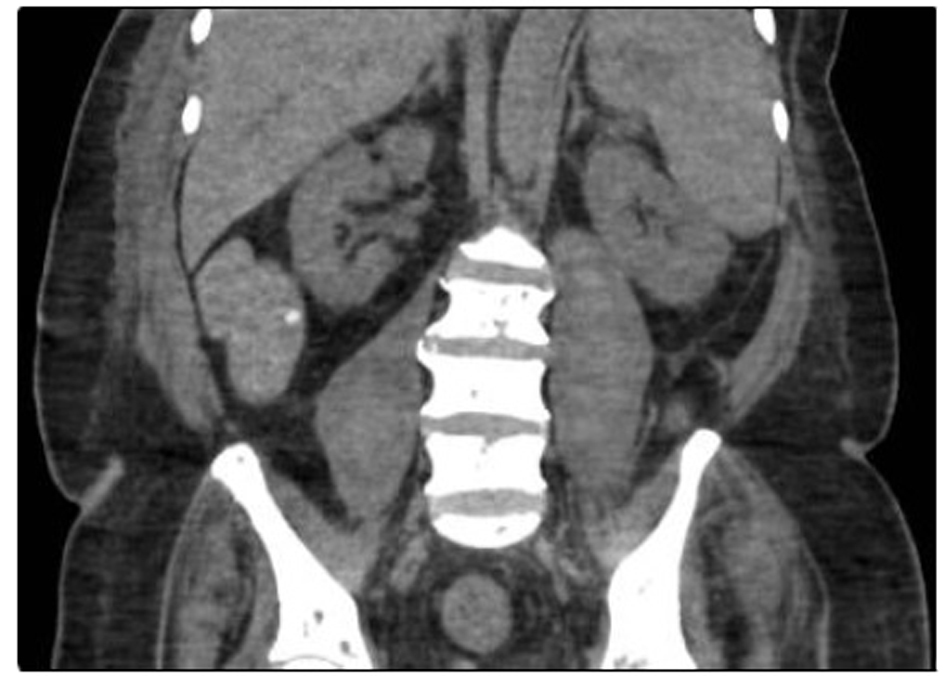

After that, non-enhanced abdomen and pelvis CT scan was performed and showed heterogeneous organized collections identified along the right and left psoas muscles causing focal contour bulge representing hematoma, with the volume reaching approximately up to 100 mL on the right side and 150 mL on the left side. There is minimal fat stranding surrounding the psoas muscles, more significant on the left side (Fig. 3, 4).

![]() Click for large image | Figure 3. There are heterogeneous organized collections identified along the right and left psoas muscles causing focal contour bulge representing hematoma. |